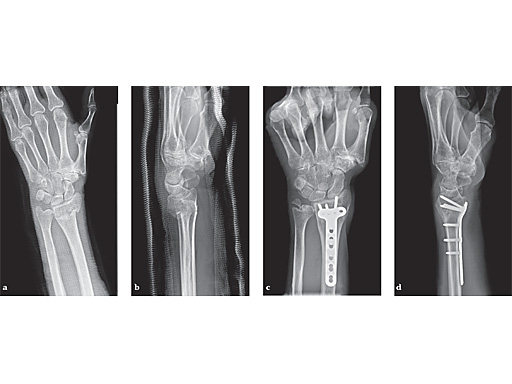

63-year-old female with skiing accident. Full motion and function was regained after 4 weeks.

ab Preoperative x-rays.

cd X-rays 6 months postoperatively.